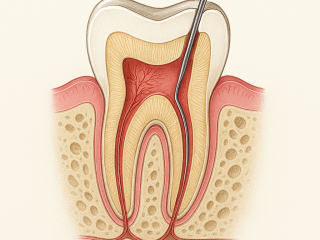

Endodontie

Traitement des Racines

Sauver une dent qui ne peut plus être soignée simplement.

L’endodontie intervient lorsque la pulpe de la dent (le nerf) est touchée, soit par une carie profonde, soit par un choc. Pour éviter l’extraction, nous désinfectons l’intérieur des racines et les scellons de manière hermétique. C’est l’étape ultime qui permet de conserver votre dent naturelle sur l’arcade et d’éviter son remplacement par un implant ou un bridge.